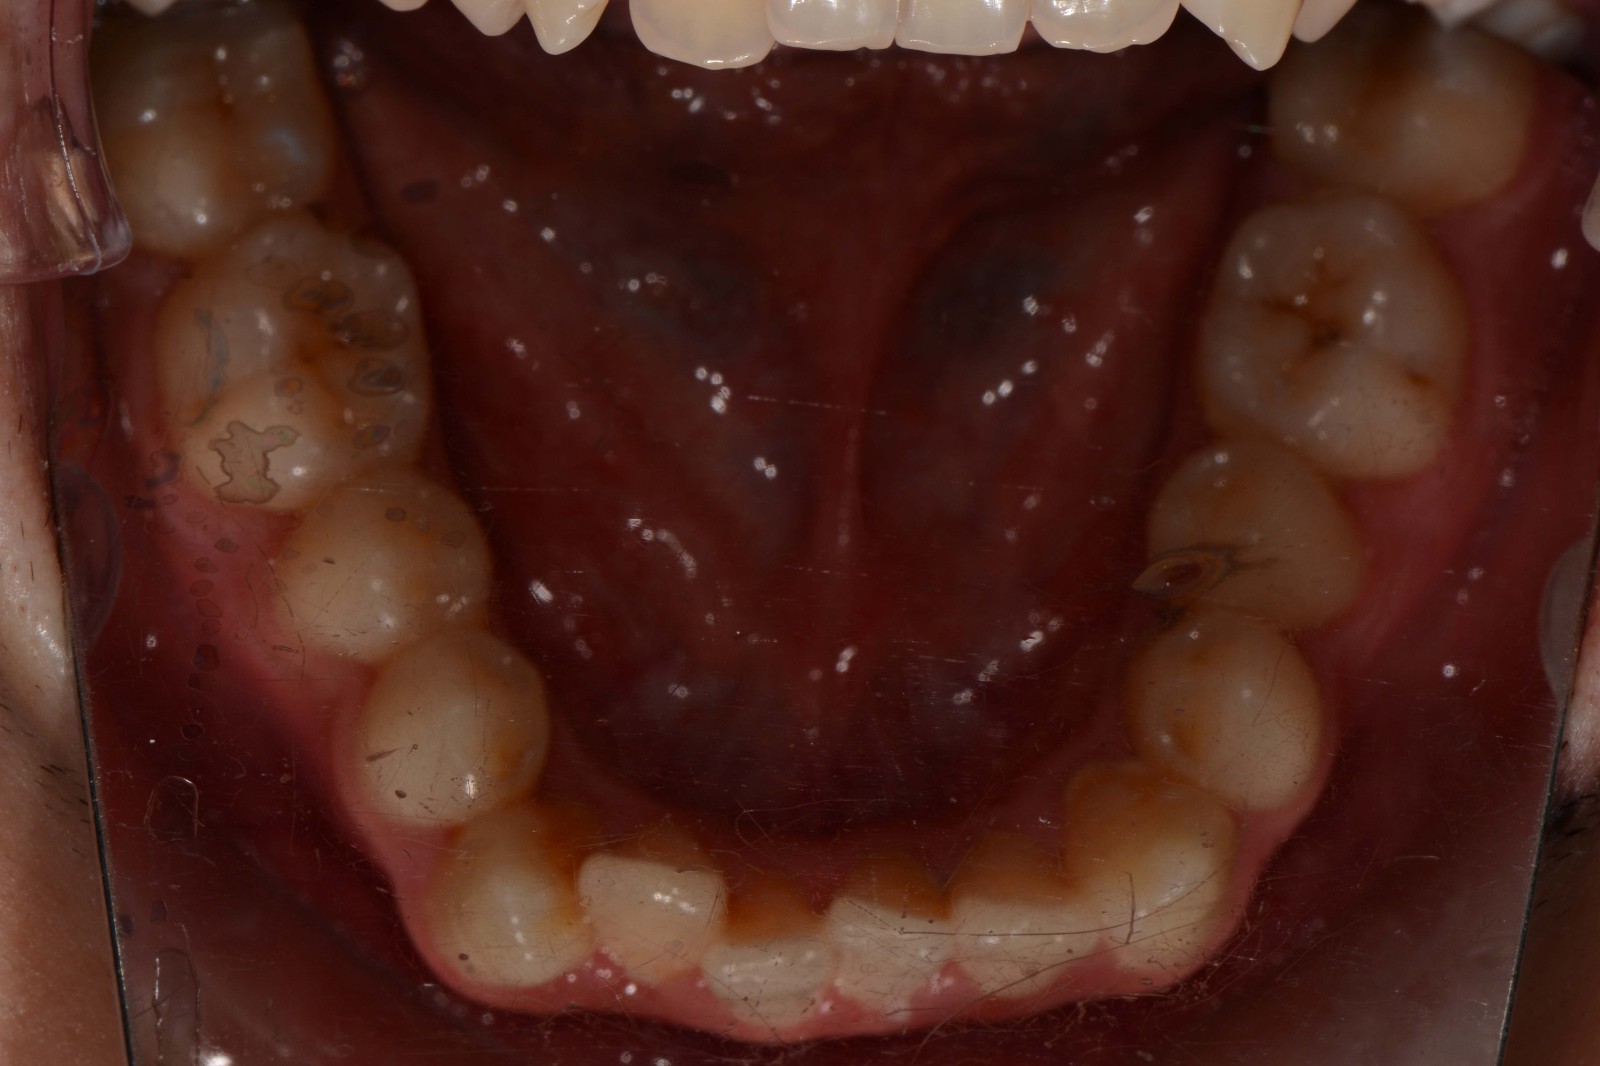

检查:拍摄口内面像照片,拍摄全景片侧位片,口扫,上下颌I-II度拥挤,中线不齐,局部反合,磨牙基本中性关系,上下前牙比较直立。

诊断:安氏I类错颌畸形

治疗方案:不拔牙矫治,适量扩弓,唇倾前牙排齐整平上下颌牙列,视情况做IPR,调整覆合覆盖,精调,保持,定期复查。

矫治前: